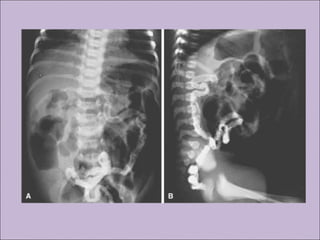

A) Intestinal: íleo meconial, síndrome da obstrução

intestinal distal, prolapso retal.

Íleo meconial

Íleo meconial

A) Intestinal: íleomeconial, síndrome da obstrução intestinal distal, prolapso retal. B) Pancreática: insuficiência pancreática, pancreatite recorrente. C) Hepática: doença hepática crônica D) Nutricional: hipodesenvolvimento pôndero-estatural , hipoproteinemia e edema, complicações secundárias à deficiência de vitaminas lipossolúveis. Doença gastro-intestinal e nutricionalDoença gastro-intestinal e nutricional Rosenstein. J Pediatr. 1998;132:389-95